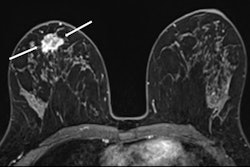

MR image from a 55-year-old patient with triple-negative breast cancer from training set. (A, above) Axial postcontrast T1-weighted image from baseline MRI exam shows unifocal enhancing mass (unifocality: positive). (B, below) Axial postcontrast T1-weighted image from MRI examination per-formed after one cycle of neoadjuvant chemoimmunotherapy shows >37% reduction in lesion size (early tumor shrinkage: positive) and development of non-enhancing region within lesion (percentage enhancement reduction: positive).ARRS

The researchers reported the following independent predictors of complete pathologic response in the training set: tumor unifocality (odds ratio [OR] = 7.2, p = 0.001) on pretreatment MRI, early tumor shrinkage ≥ 37% (OR = 9.7, p < 0.001), and percentage enhancement reduction (OR = 9.7, p < 0.001) on early-chemotherapy MRI.

Finally, in SHAP analysis, global importance for model predictions was highest for percentage enhancement reduction (mean absolute SHAP value, 0.42), followed by early tumor shrinkage (0.32) and unifocality (0.21).